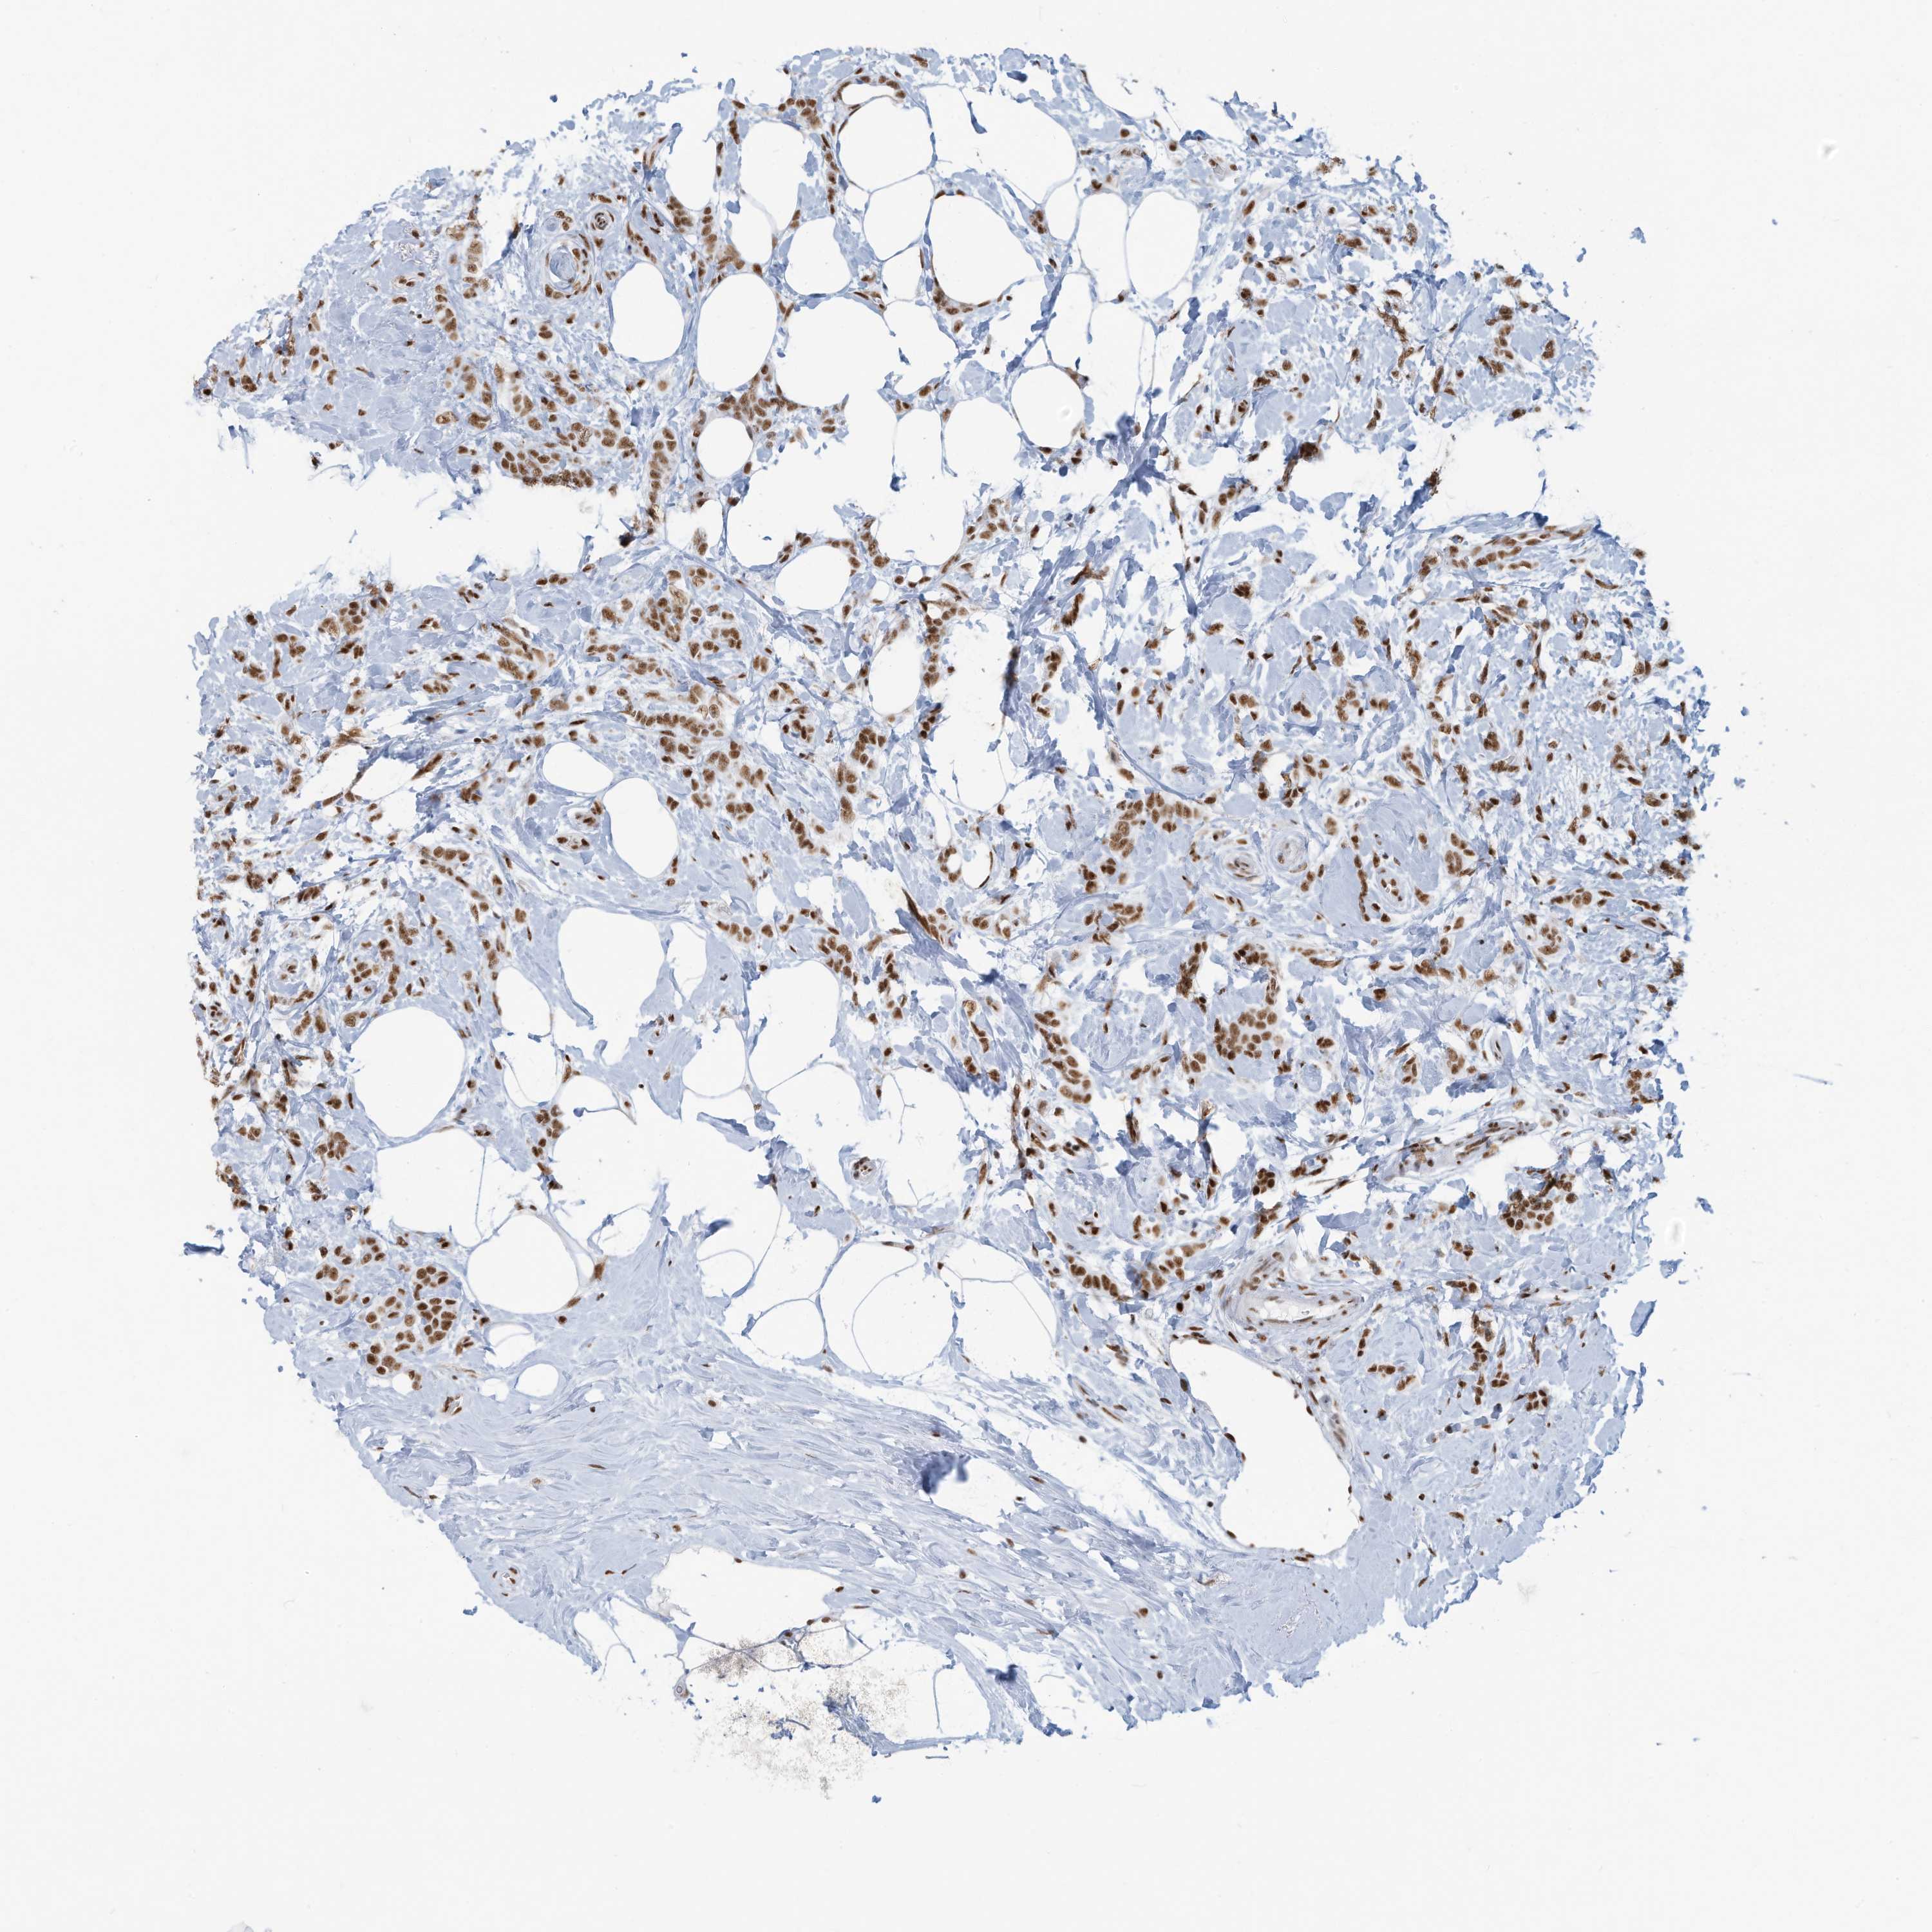

CANCER BREAST CANCER Show tissue menu

BRCA TCGA BRCA VALIDATION PROTEIN EXPRESSION